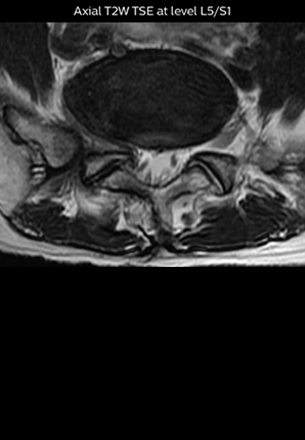

“The intra-luminal signal of veins, especially around the intervertebral space, can be suppressed well with NerveVIEW. As a result, we can easily observe the detailed nerve structure around the posterior ganglion,” he says. “This is why we use 3D NerveVIEW for intraforaminal stenosis and extraforaminal stenosis/herniation (lateral disc herniation). On the other hand, if herniation is suspected to exist inside the dorsal root ganglion (DRG), balanced TFE or ProSet-FFE is applied. NerveVIEW is not suitable for evaluating the median type of herniation.” The SE-EPI DWI-based method for MR neurography works well for large FOV exams like whole-body MRI, but focal examination of nerves is often limited by the attainable spatial resolution (both inplane and slice direction) and geometric distortion. “3D NerveVIEW achieves higher in-plane resolution – close to our other routine spine sequences – and the source images can be used instead of adding a fat-suppressed T2-weighted sequence,” Tanji says.

“Recently, the two surgical methods extreme and oblique lateral interbody fusion (XLIF and OLIF) have become mainstream for minimally invasive treatment of lumbar spinal canal stenosis and intervertebral foramen stenosis. With these surgical techniques, the spine is approached from the flank, and prior knowledge of the exact anatomy of the lumbosacral plexus would be extremely helpful. To that end, high slice resolution (less than 1 mm acquisition) that enables sharper sagittal MPR images will be needed.”

“For both brachial and lumbar plexus, we are currently using a 230 mm FOV and voxels of about 1 x 1 x 2 mm acquired (1 x 1 x 1 mm reconstructed). This provides us a good representation of the nerves, even though this FOV is relatively small. Regarding the inplane resolution, we hope to be able to bring that down to 0.7 mm, similar to our typical 2D multislice T2W images,” says Tanji.

Implementing NerveVIEW without lengthening exam time “The source images of NerveVIEW exhibit a contrast similar to STIR or fat-suppressed T2-weighted images. So, in our neurography exams we are replacing the 2D T2-weighted coronal sequence with 3D NerveVIEW. With this, we add a lot of useful information without adding scan time. This is important for patients with severe lower extremity symptoms, as they often find it difficult to maintain still during the whole MRI examination, so the exam should be as short as possible.” “We have currently implemented 3D NerveVIEW on our Achieva 3.0T dStream MRI system only. Because the 3D NerveVIEW method is based on a background signal suppression technique, we decided to use the high SNR of our 3.0T MRI system for obtaining the best possible visualization of peripheral nerves,” says Tanji. “Where NerveVIEW of the lumbar plexus is currently used as a subroutine scan for patients with strong lower limb symptoms, its use for visualization of the brachial plexus, is currently limited to special cases such as schwannomas and neuritis, usually only 1 or 2 cases per month.”